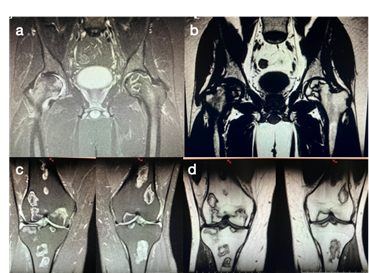

Las radiografías de pelvis 2015 no muestran alteraciones en la morfoestructura ósea. En 2016 aparecen imágenes radiolúcidas rodeadas de áreas escleróticas epifisarias bilaterales, con perdida de la esfericidad normal de la cadera derecha, por último en 2017 se observan ambas caderas afectadas, predominando el hundimiento epifisario, el colapso y alteración de la esfericidad de la cabeza femoral así como la pérdida de la luz articular. Figura 1.

Se puede ver la rápida evolución de la enfermedad en la cabeza femoral, pasando de un estadio I de la clasificaciones Ficat y Arlet en 2015, a un estadio II/III en 2016 y finalizar en el estadio IV en 2017. Tabla 1.

Figura 3: RNM de pelvis y rodillas. Stir coronal pelvis (a), T1 coronal pelvis (b), Stir coronal rodillas (c) y T1 coronal rodillas (d).